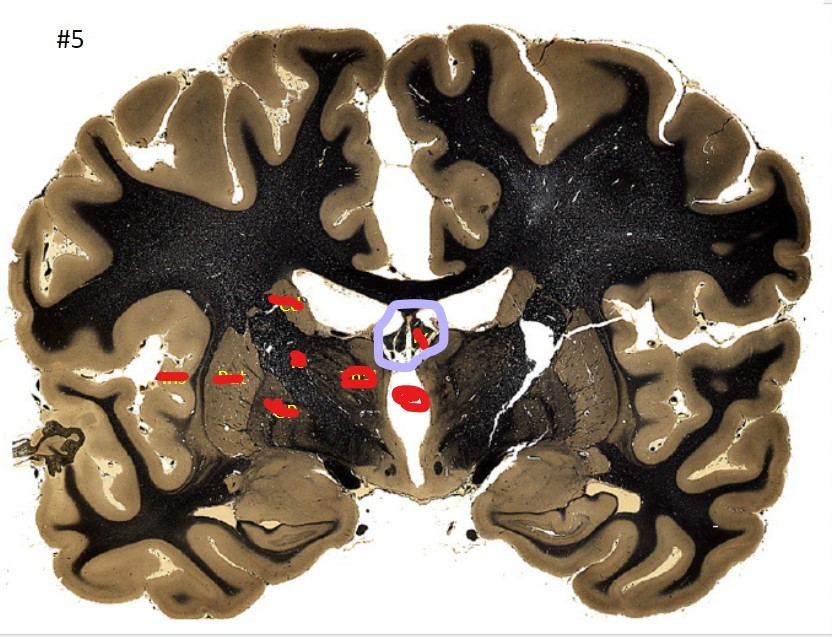

Q

what is the circled area (#5)?

A

the caudate nucleus

21

the 3rd ventricle

22

23

the globus pallidus

24

25

the internal capsule

26

the putamen

27

the amygdala

28

the beginning of the hippocampus